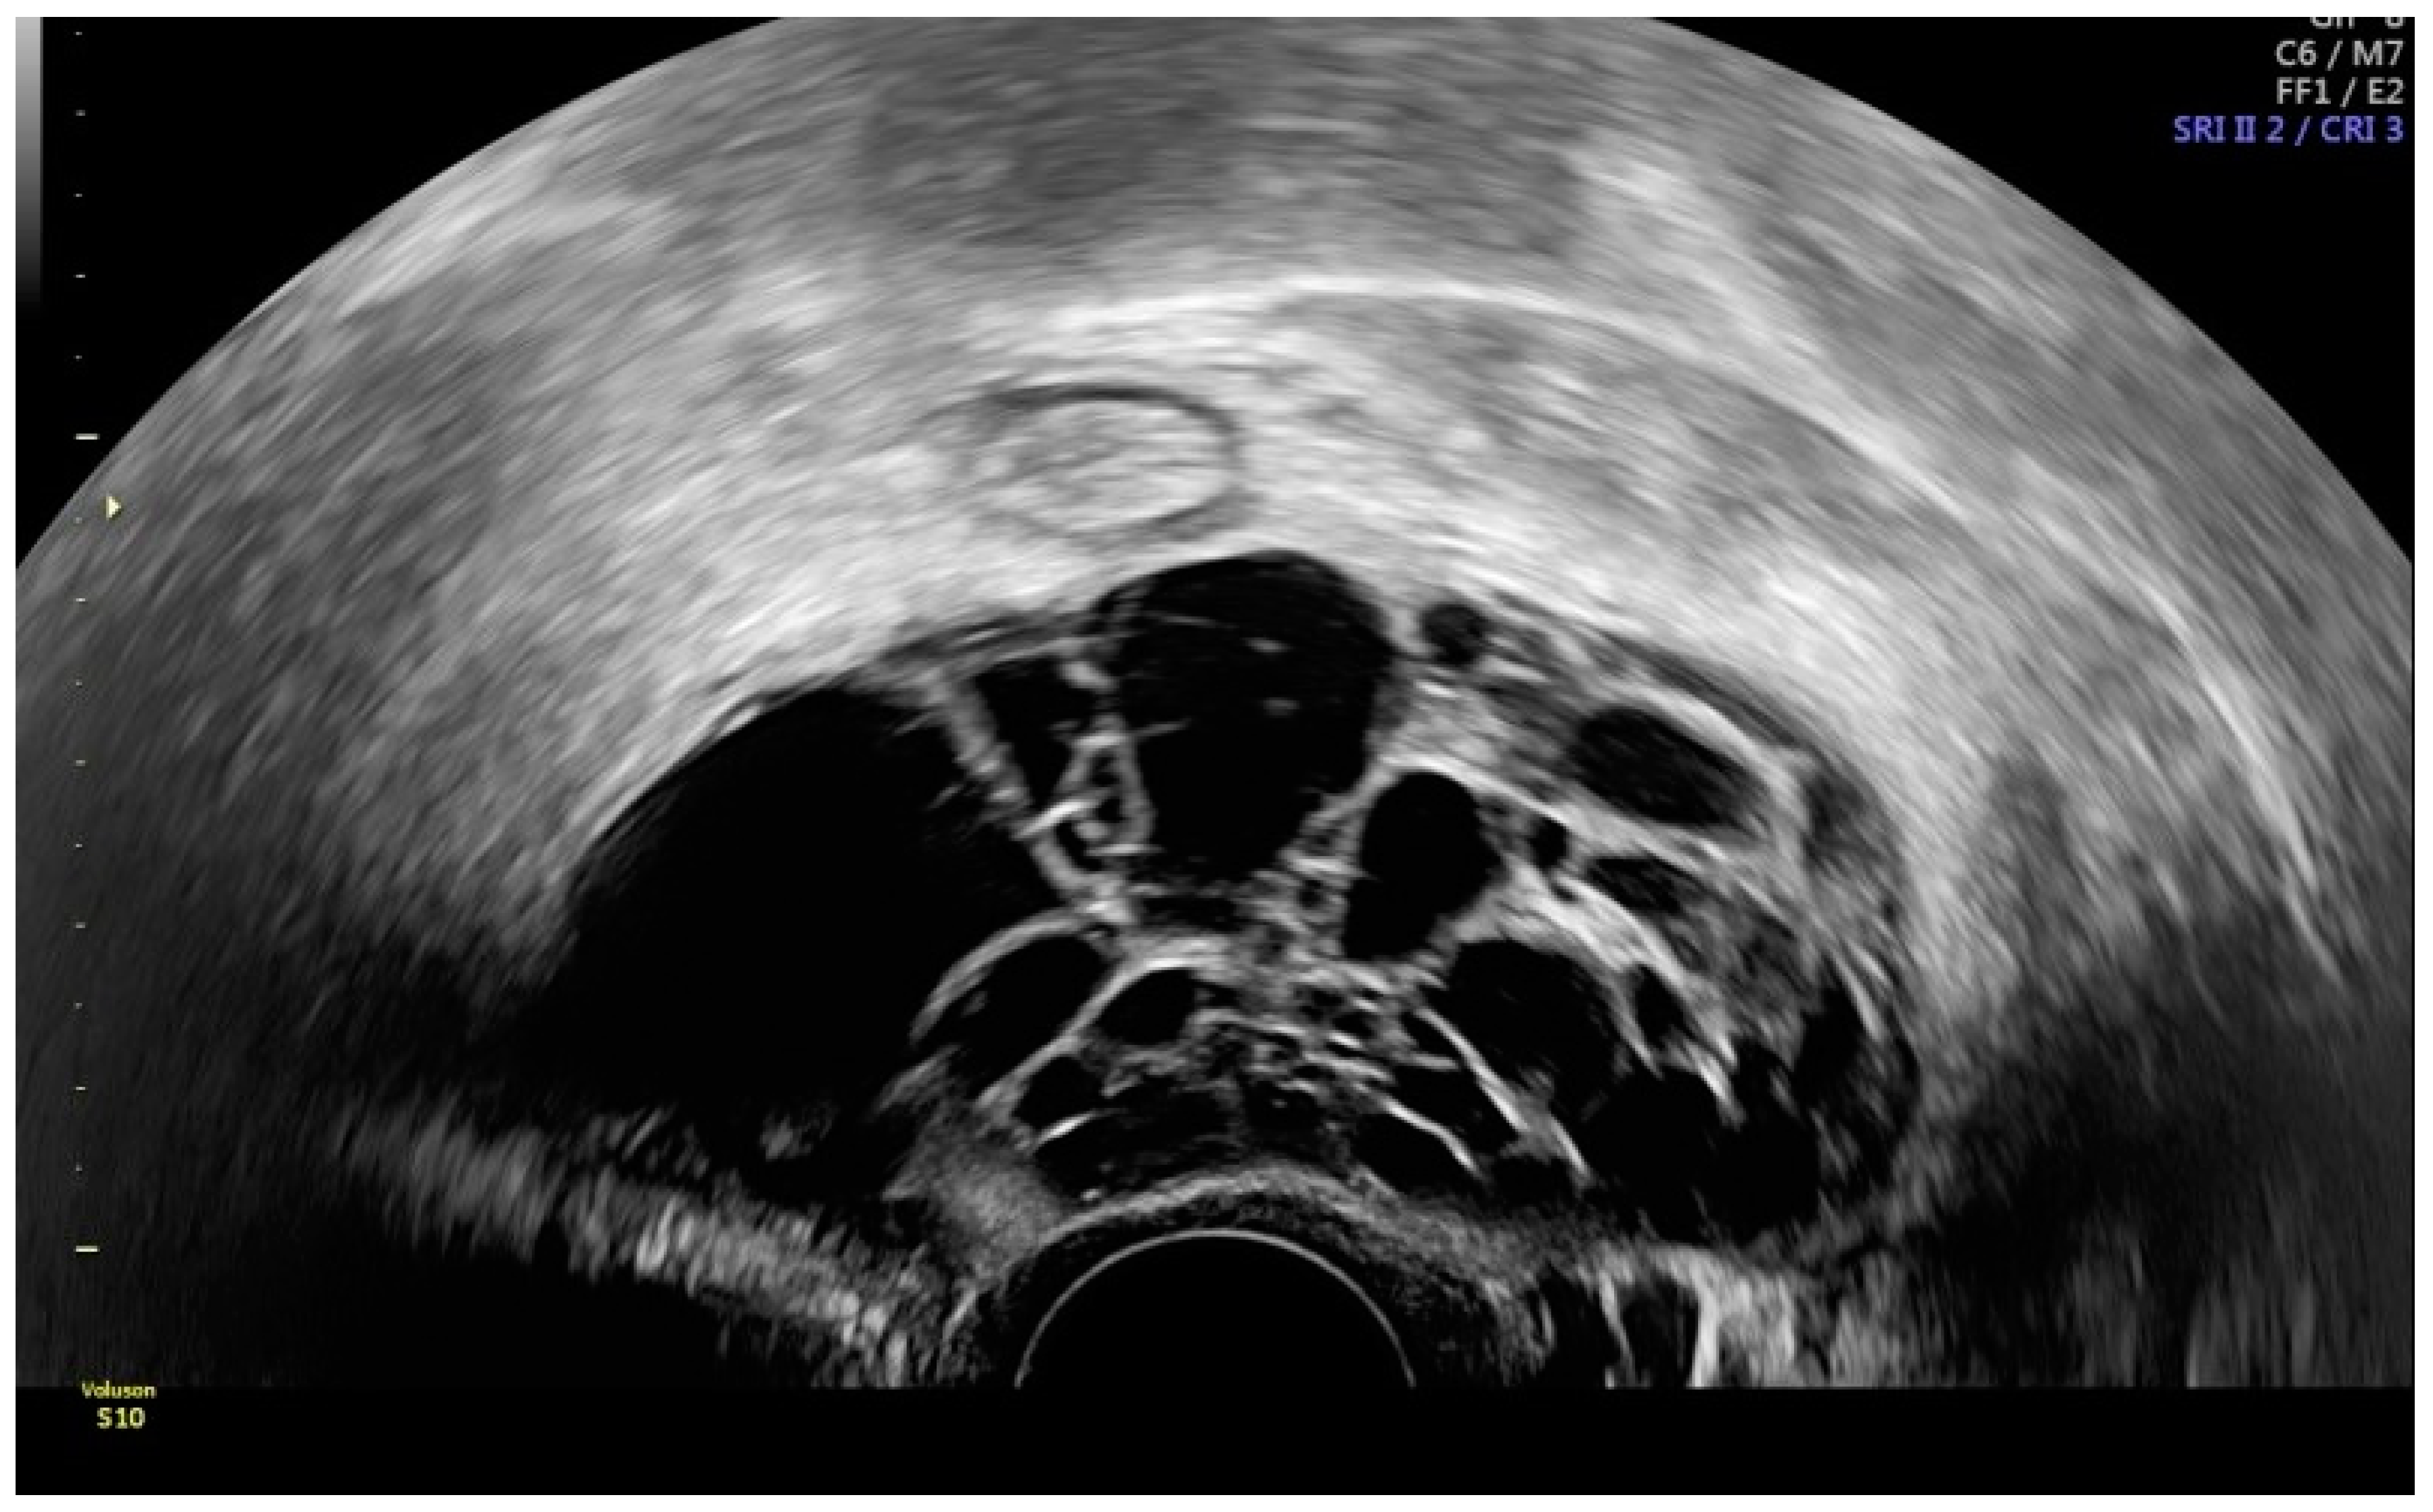

5. Lymphatic Imaging